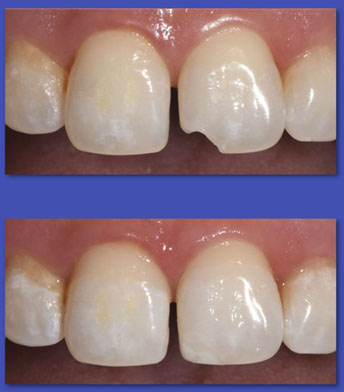

9. ESTÉTICA DENTAL

La estética  actualmente, en nuestra sociedad marca la diferencia. Una bella sonrisa ( con dientes hermosos y sanos ) nos abre puertas en  todo lugar y circunstancia, de ahí la importancia. Una sonrisa perfecta se puede lograr recurriendo a procedimientos de :  Blanqueamiento o Clareamientos dentales, Carillas de Cerámica, Ortodoncia, Remodelación de encías,etc.

ANTES

DESPUÉS